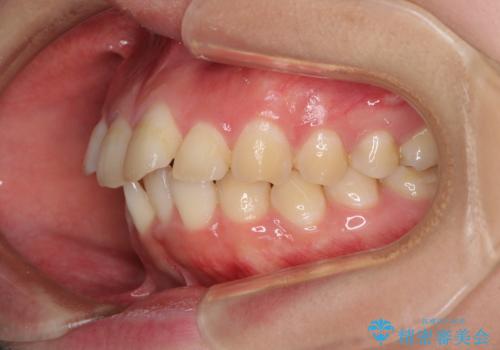

4本の歯を抜歯したことで、飛び出していた口元が引っ込み、横顔が大きく改善されました。

咬み合わせが悪化することのないようにスペースを閉じていくことができ、比較的スムーズに治療を進めることができました。